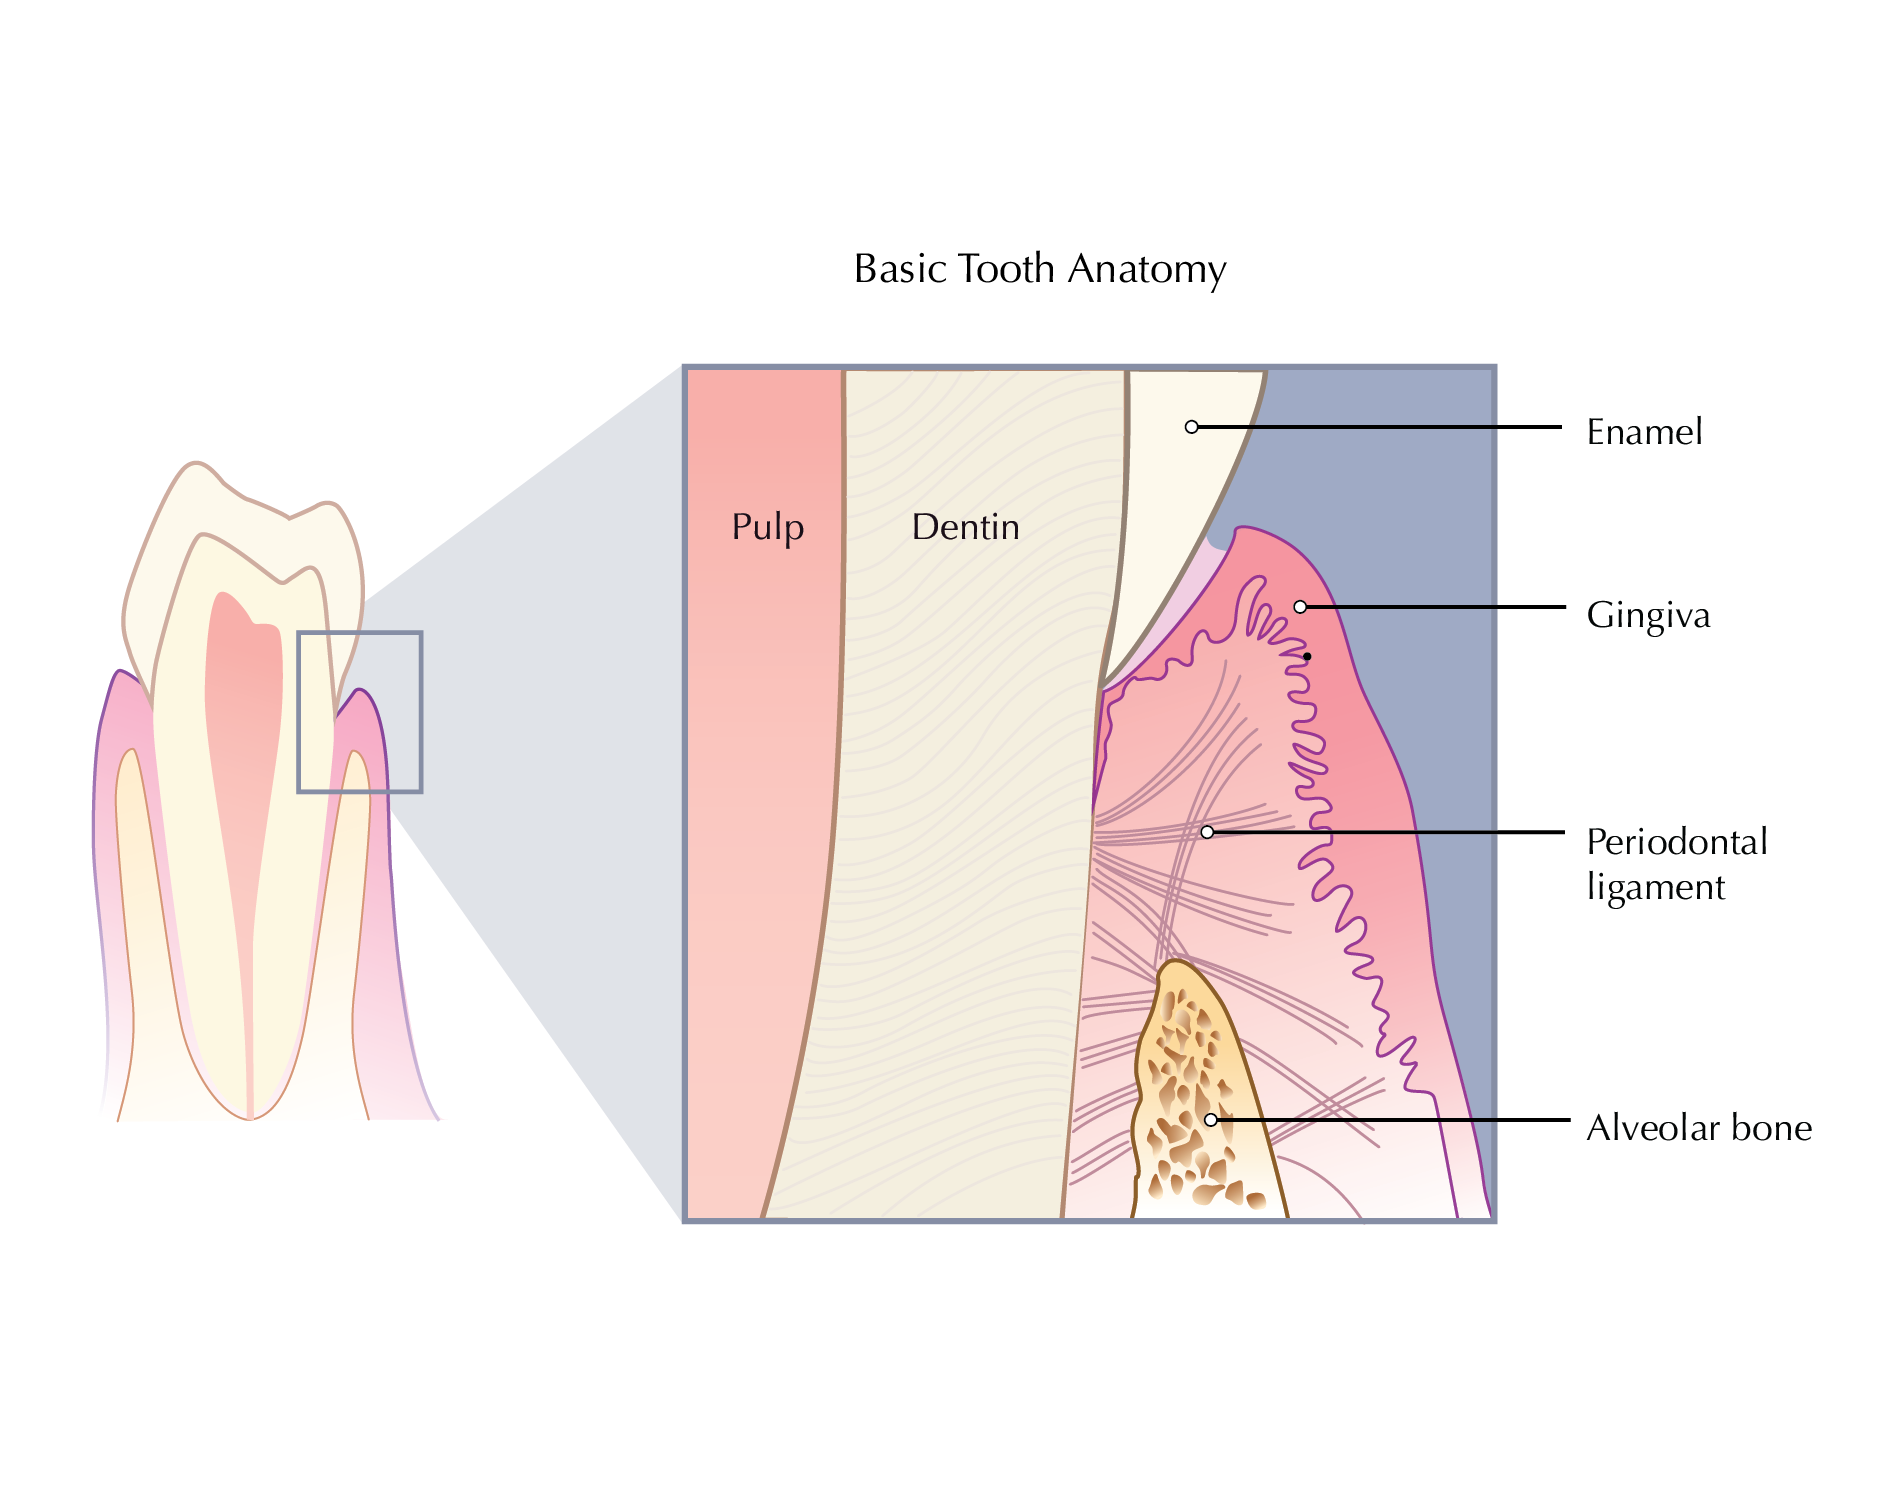

Informative, straightforward illustrations can help patients better understand their medical condition, treatments and procedures. Doctors and healthcare providers can use illustrations to communicate more effectively and reduce a patient’s anxiety about their condition or treatment.

Instructional illustrations are used to teach or explain medical information to a specific target audience. Examples include;

Publications including textbooks and journals.